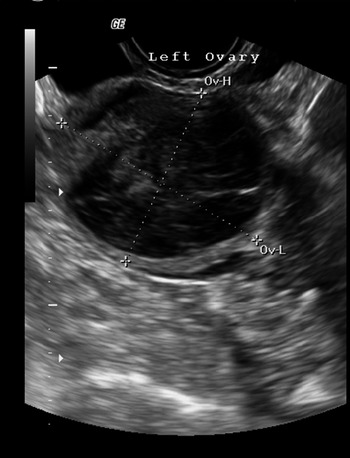

Do twins take longer to show up on ultrasound. A twin ultrasound at 6 weeks needs to be done vaginally to detect twins this early in your pregnancy. There are basically 2.

You can look for and detect the two outer sacs even though you might not be able to discover heart beats yet. This is when youll know for sure whether or not your expecting twins. I think its harder to miss with the external wand but the vaginal ultrasounds dont have the same range of motion.